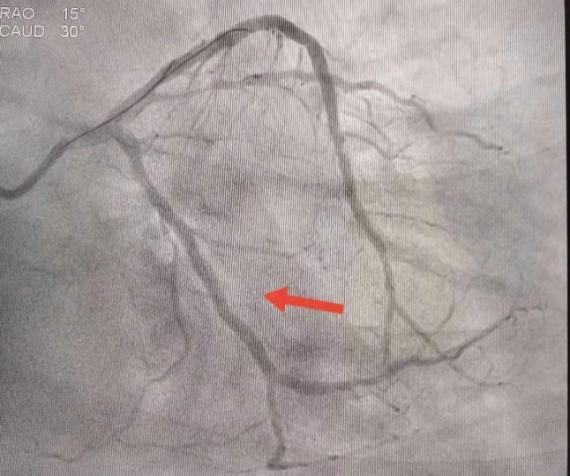

王勇带领介入团队争分夺秒,从血管穿刺到冠脉造影完成仅用时10分钟左右。造影结果显示,刘先生回旋支急性闭塞病变,前降支重度狭窄病变。

团队密切合作,导丝通过、球囊扩张、支架置入,大约5分钟左右,闭塞的血管得以开通,刘先生胸闷胸痛的症状消失,生命危机得以解除。